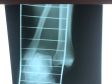

18.09 был перелом наружной лодыжки правой голени, вывих правой большеберцовой кости, оскольчатый перелом с/з малоберцовой кости со смещением к/отломков. 24.09 травматолог доделала гипс, но с того времени отёк спал ещё больше. Сейчас гипс болтается, не спадает, конечно, но почти вся ладонь может пролезть внутрь. Вертикально ногу держать очень больно, только горизонтально. Стоит ли обратиться к травматологу для коррекции гипса? Или так и должно быть? Следующий плановый визит только 10.10.